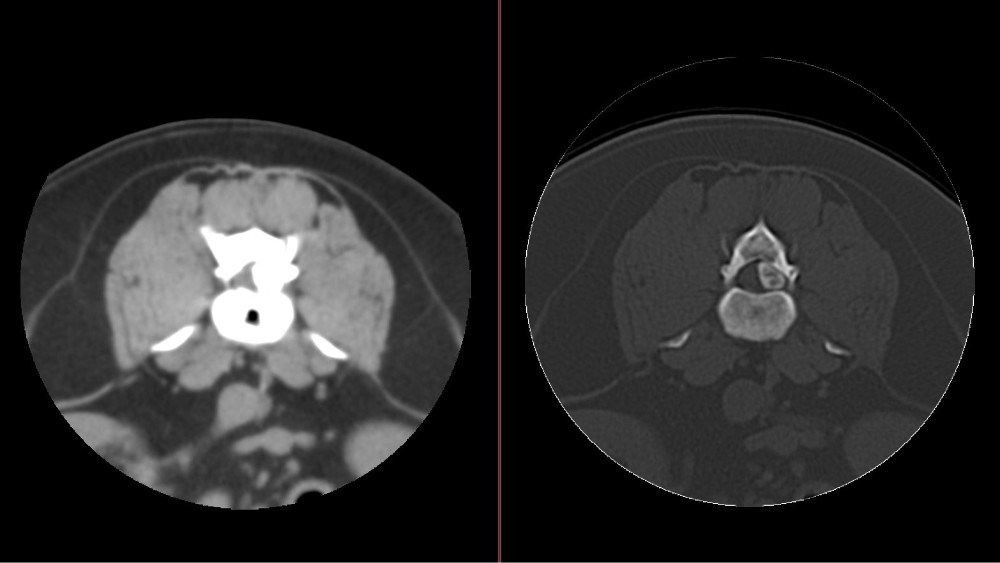

CT Bandscheibenvorfall Lendenwirbelsäule postoperativ

CT Bandscheibenvorfall Lendenwirbelsäule Quer- und Längsschnitte – links vor der OP – rechts postoperativ: vor der OP wird die Kontrastmittelsäule durch den Bandscheibenvorfall verdrängt – nach der OP kann sich die Kontrastmittelsäule ohne Verdrängung anlegen